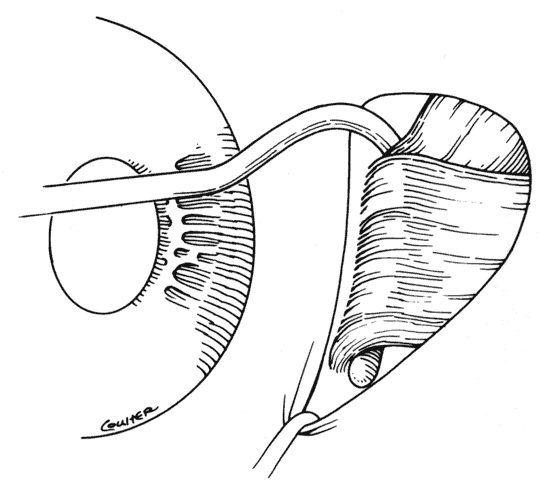

In some situations, a portion of a horizontal rectus may be left at the insertion site (Figs. 9 and 10). The muscle is usually split at the time of the initial procedure, and this can cause a shift of the distribution of force at the insertion and cause vertical misalignment. The pattern of the strabismus and the details of the previous surgery should provide clues to the problem and allow a logical approach for correcting the vertical deviation. Suspicions should be confirmed by careful dissection and exploration of the region of the muscle insertion. The importance of careful evaluation and elimination of mechanical restrictions cannot be overemphasized.4,10

Fig. 9. Residual exotropia or hypertropia can occur if a portion of the lateral rectus muscle is not recessed with the first procedure. To prevent this, care must be taken to incorporate all portions of the tendon when recessing an extraocular muscle.

Fig. 10. The pole test, or sweeping a Stevens muscle hook anterior to the insertion, will ensure that the entire tendon is on the Jameson muscle hook.